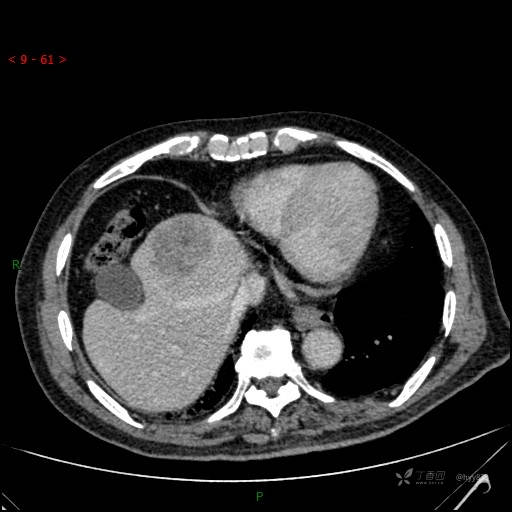

延迟期

img